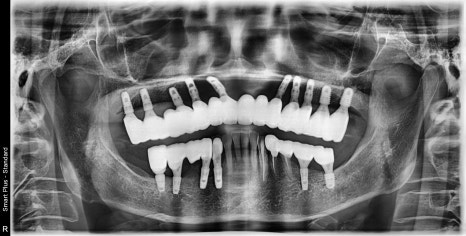

드디어 중간 기둥이 들어가고 임시치아를 쓰는 기간을 갖는 단계입니다.

이 시기가 은근히 지루하고 귀찮은 시기입니다.

오랫동안 틀니를 사용하셨기 때문에 턱관절을 안정화 시키기 위해

저는 환자분께 자주 뵙자고 말씀드립니다!!!

오실때마다 턱의 위치가 변하면서 교합이 변하기 떄문에

조정해드리고 사용하는 과정을 반복 했습니다.

이 기간에는 치아 모양이나 안모의 모양을 보며 최종 보철의 디자인을 위해 중요한 기간입니다.

몇달이 지나고 이젠 턱관절도 안정이 되면

부위를 나눠서 최종 보철을 제작하기 시작합니다.

한쪽씩 보철을 제작하면서 최종보철물도 수정과 적용을 통해

기능, 심미를 모두 만족할만하게 완성했습니다.